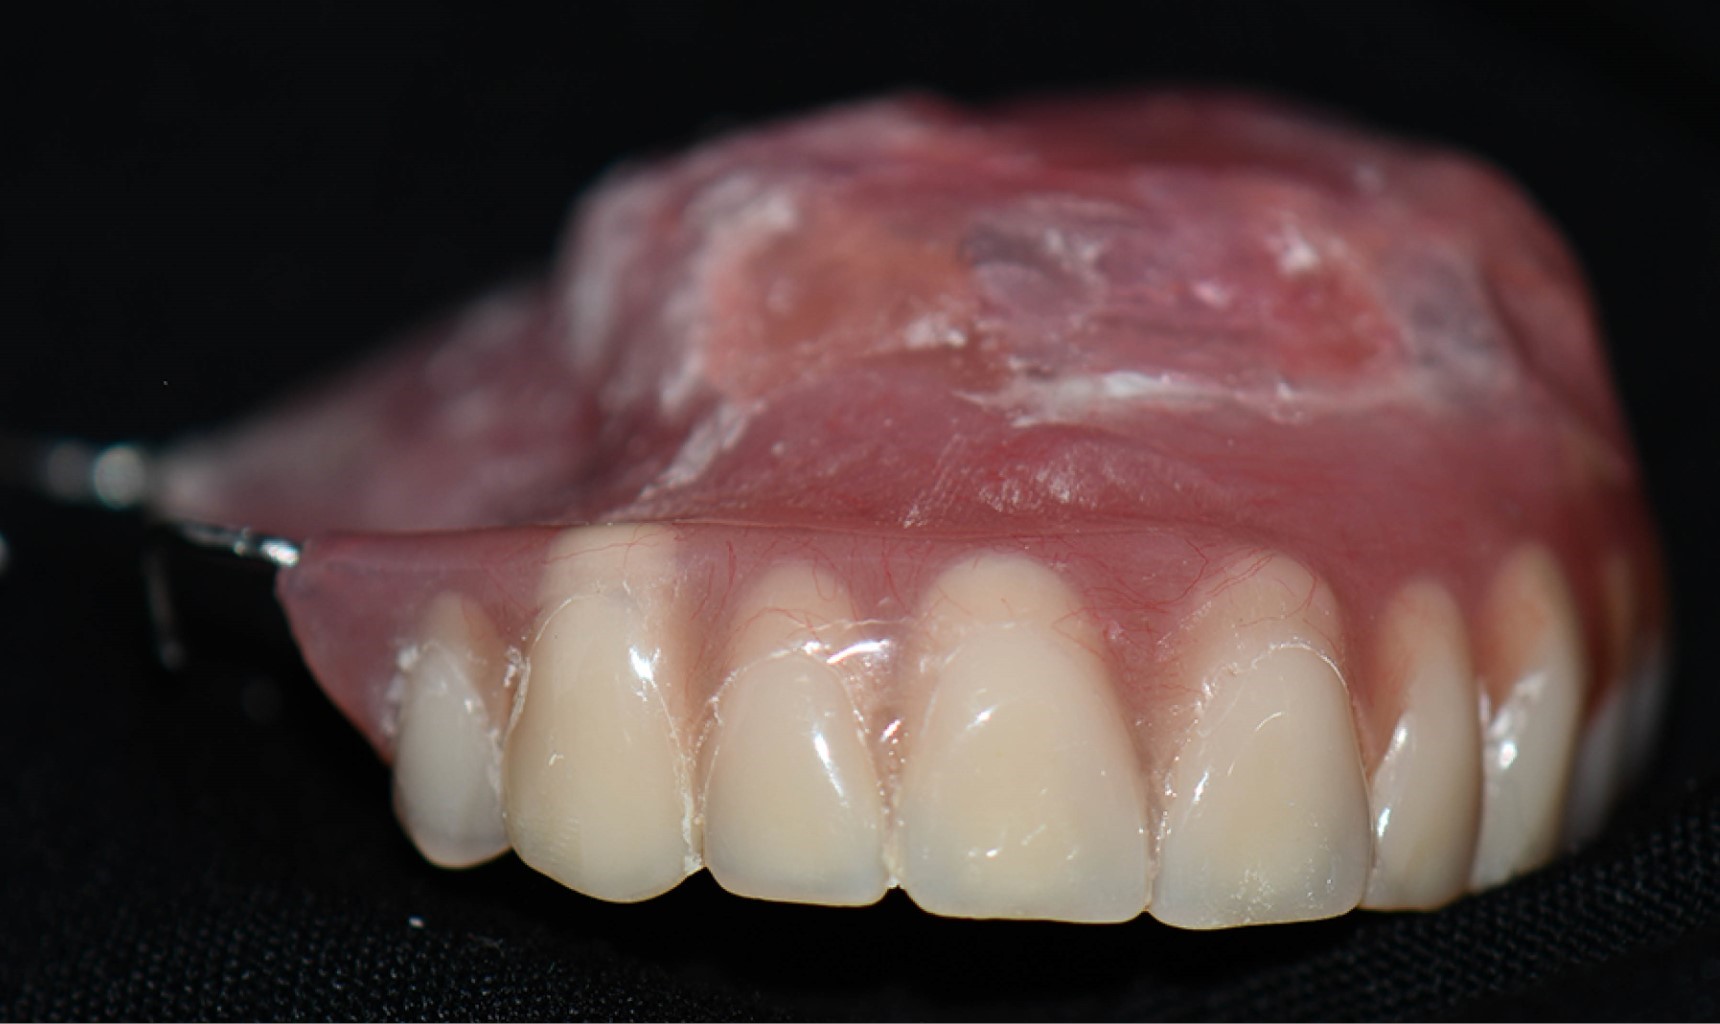

El paciente acudió a cita de control siete días después para evaluación del proceso de cicatrización (Figura 5). Después fue referido al servicio de prótesis maxilofacial para la elaboración de un obturador. Se optó por la fabricación de una prótesis parcial removible modificada con bulbo obturador, correspondiente a un defecto maxilar clase VI de Aramany. Tras una planeación cuidadosa de las superficies de apoyo, retención y estabilización, se utilizó Ufi Gel SC como material de rebase, lo que permitió restaurar la deglución, fonética y estética, contribuyendo así a mejorar la calidad de vida del paciente (Figura 6).

En la actualidad, el paciente continúa en seguimiento periódico para evaluación de la adaptación y mantenimiento de la prótesis (Figura 7).

Figura 6

Figura 7